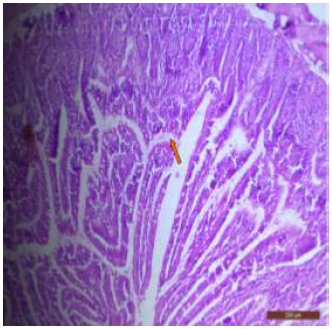

Light Microscopic Examination

The duodenum of control rat showed histological features such as presence of different layers such as mucosa, submucosa, muscularis and serosa. The lining of epithelium of microvilli was composed of many cell types such as goblet cells, Paneth cells and absorptive columnar epithelial cells (Figure 1). Brünner’s glands were seen in the submucosal region of the duodenum which secrete alkaline fluid containing mucin (Figure 2). The rats treated with 600mg/kg b.w./day for 40 days revealed thickened and scattered villi (Figure 3). Hypertrophy of goblet cells and damaged crypts were also observed. (Figure 4). The necrotic Brünner’s gland showed inflammation and dilation of spaces (Figure 5).

Figure 1: T.S. of duodenum of control rat showing crypts (↑), closely packed microvilli (↑), well developed submucosa and muscularis externa. H&E × 100.

There was disruption in the villus architecture with crypt loss. The submucosa, muscularis externa and outer serosa were undifferentiated and were not clearly seen (Figure 6). There was marked villous atrophy, characterized by the shrinking and flattening of the intestinal villi. Additionally, mucosal erosion was also evident, indicating the wearing away of the protective mucosal layer (Figure 7). The duodenal tissues showed widespread disruption, with visible signs of structural disorganization and inflammation (Figure 8). The jejunum of control rat showed distinctive layers, i.e; mucosa, submucosa, muscularis and serosa (Figure 9). The jejunal mucosa was formed of epithelium, lamina propria and muscaris mucosa. The mucosa appeared as finger like projections with a core of connective tissue covered with enterocytes. Goblet cells were also seen in between the cells which are specialized type of epithelial cells, secrete mucus to neutralize the acids produced by stomach (Figures 10,11).

Figure 3: T.S. of duodenum of rat treated with 600 mg NaF/kg bw/day for 40 days showing thickened and scattered villi. H&E × 100.

Figure 4: T. S. of duodenum of rat treated with 600 mg NaF/kg bw/ day for 40 days showing bulbous and swollen villus tip (↑), damaged crypts (↑) and hypertrophy of goblet cells (↑). H&E × 100.